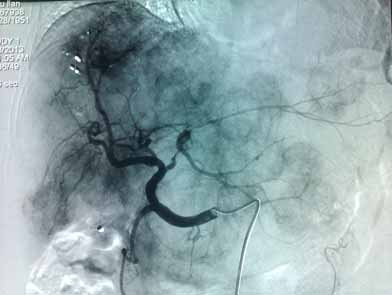

肝动脉分支血管增多、增粗,实质期肝脏可见多发大小不等结节状肿瘤染色

胃左动脉超选择造影见肿瘤血管增多、杂乱,示块状肿瘤染色